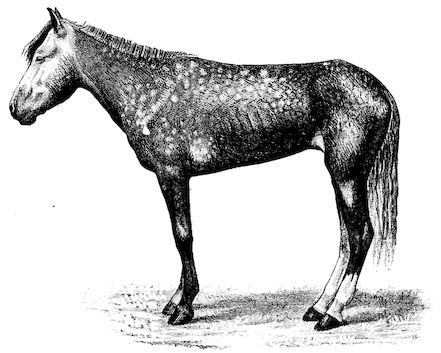

Fig. 1.—Rachitis in a young goat.

Rachitis is a disease of youth, and is common both to the human species and to all domestic animals. It is characterised by irregularities in development and by imperfect consolidation of the bones. The boundary between rachitis and osseous cachexia is difficult to define and in fact at the present moment the two diseases can scarcely be defined with exactitude. Rachitis again is often complicated with softening of the bones, disease of the limbs, arrested development, etc., but it must not be forgotten that although the irregularities in ossification and development of the skeleton are the symptoms most striking to the eye, they do not stand alone, and that from the point of view of development all the tissues, including the muscles, are more or less affected and that most of the physiological functions such as digestion and the secretion of urine are deranged.

Symptoms. The onset is absolutely insidious and the diagnosis of rachitis is never made until nutrition has long been abnormal.

This disturbance of nutrition is revealed by irregularity and abnormality in appetite, by difficulty in rising and moving about, and by the animals lying down for long periods. The subjects are feeble, sluggish and badly developed.

Next supervenes the second phase characterised by deformity of bones. This is of two kinds—deformity in the neighbourhood of joints (deformity or enlargement of the epiphyses) and deformity of the diaphyses. The former results from irregularity in ossification of the articular cartilages. The latter is followed by loss of rigidity in the bones of the limbs which, under the influence of the body weight and of muscular contraction, bend in different directions.

The bones appear of increased thickness principally towards the 6articulations. The latter are deformed, and on palpation are found to be surrounded by uneven and irregular growths.

The front limbs are distorted. In young pigs, lambs, and less frequently in foals, calves and dogs, the jaws become deformed, and mastication is rendered difficult.

The vertebral column may also be affected, and lordosis (bending downwards of the back) or skoliosis (lateral bending of the back) is somewhat frequent.

Cyphosis, or upward bending of the back, seldom occurs, and when seen, sometimes results from disease other than rachitis.

General development is always interfered with and the young creatures are generally dwarfed.

The digestive apparatus is disordered, the appetite is irregular and sometimes depraved, while indigestion, gastritis, and enteritis are not exceptional. Physiological and pathological research has shown that the quantity of phosphoric acid eliminated in twenty-four hours in a rachitic child is double the quantity passed by a healthy infant. The amount of urea in the urine (which is a criterion of nutrition, and usually varies in proportion to the amount of food ingested) is, on the contrary, diminished even when highly nitrogenous food is given, thus suggesting diminution in nutrition.

Lesions. The lesions are represented by abnormal and irregular thickening around the interarticular cartilages. The cartilage is thickened, compressible, very spongy and without regular ossification. Diffused periostitis exists principally towards the extremities of the bone. Beneath the periosteum the surface of the bone appears rough and softened. On section the medullary canals are seen to be enlarged and filled with marrow of a gelatinous character. The Haversian canals are dilated, and the entire tissue appears very vascular. Chemical analysis proves that the mineral constituents of the bone, particularly the phosphates, have diminished by one-half; the organic constituents on the other hand are increased in a similar ratio, but the ossein is abnormal. Ossification has, in a word, been incomplete.

7Diagnosis. Diagnosis presents no difficulty except in the early stages before deformity has occurred.

Rachitis can scarcely be mistaken for any other condition except perhaps infectious rheumatism, but the rapid course of the disease in the latter case, the persistence of fever and the swelling of the joint cavities sufficiently differentiate the conditions provided care is exercised.

Prognosis. From an economic point of view the prognosis is very grave for if the lesions are extensive there is nothing to be gained by keeping the animal.

Treatment. Treatment differs very little, whether the animals are still being suckled or have been weaned. In the former case it is necessary to improve the quality and chemical constitution of the mother’s milk by giving food, richer both in mineral salts and in nitrogenous material.

Cooked grains, milk, and forage of good quality should be given freely. When the mothers are exhausted and anæmic it is better to feed the little animals artificially or to change them to a foster-mother. Those already weaned should be given good rich milk, eggs, boiled gruel, and drugs, such as the phospho-chlorate of lime, 1 to 1½ drachms per day (for a calf); lacto-phosphate of lime, 1 to 1½ drachms; bi-phosphate of lime, 1 drachm, or simply ordinary phosphate of lime. Oil containing 1 per cent. of dissolved phosphorus may be given in doses of 1 to 2½ drachms, according to the size of the calves, but its use calls for much care, and it should only be given for alternate periods of a fortnight. The glycerophosphates are not very active. Beef meal in doses of 6 drachms to 1½ ounces and chloride of ammonium in doses of 30 to 60 grains have also been used advantageously. The above drugs, but particularly the bi-phosphate of lime and chloride of ammonium, stimulate nutrition and diminish the quantity of phosphoric acid eliminated.